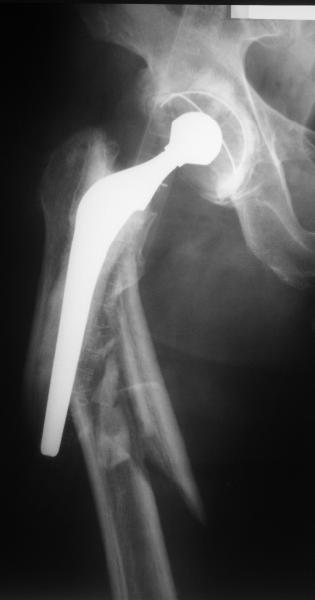

Female, rheumatoid, THA in 2003, car accident in 2006, failed plating. Nailing in Oct 2007. The nail is solid with hollow proximal part where the stem is docked. Last images are in 1 year after

nailing.

Спасибо за обсуждение. После нескольких дней тракции аппаратом сделали. Попытка закрытой репозиции не удалась из-за смещения по ширине, мешали фрагменты цемента. После их удаления репозиция получилась. Еще убрали немного цемента с ножки по латерльной стороне, чтобы обнажить 40-50 мм ее дистальной части, для плотной посадки гвоздя. Дальнейшее введение гвоздя было несложным. Протез показался нам стабильным в проксимальной части как латерально, так и медиально. Картинки в приложении.

THX for the discussion. After few days of traction by ex-fix the surgery was performed. An attempt of closed nailing was unsuccesful because of fragment translation, which was blocked by cement fragments. After removal of broken cement pieces reduction was reached "automagically". Also some cement from lateral part was removed by

chisel to expose distal 40-50 mm of the stem to allow tight fit of the nail. Further fixation by the nail was pretty easy and straightforward. Images attached. The stem looked stable in its proximal part both laterally and medially. Comments/critics are welcome.